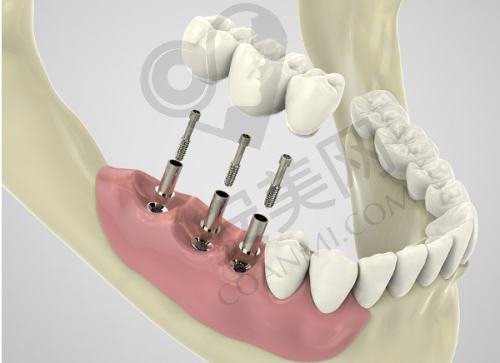

创英种植牙是一种精良的种植牙系统。它采用了高品质的种植材料,具有良好的生物相容性,能够与人体牙槽骨更好地结合,提高种植成功几率。创英种植牙的设计科学合理,模拟了天然牙齿的形态和结构,不仅在外观上与真牙几乎无差别,而且在功能上也能够接近真牙,让患者能够正常咀嚼食物。此外,创英种植牙的使用寿命较长,能够为患者提供长期稳定的牙齿修复成效。

创英种植牙的手术过程一般分为几个步骤。首先,患者需要到柳州中瑞口腔进行全方面的口腔检查,包括口腔CT扫描等,以确定患者的口腔状况和牙槽骨条件。刘轩医生会根据检查结果制定详细的种植方案。然后,在局部麻醉下,医生会在患者的牙槽骨上制备一个合适的种植窝,将种植体植入其中。植入后,需要等待一段时间,让种植体与牙槽骨充分结合,这个过程通常需要几个月的时间。之后,医生会安装基台和牙冠,完成整个种植牙的修复过程。在整个手术过程中,刘轩医生会严格遵循无菌操作原则,确保手术的安心和成功。